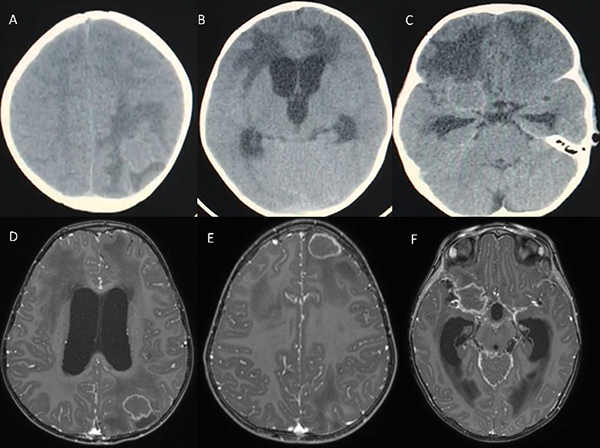

Paciente femenina de 2 años, sin antecedentes de relevancia, quien consultó en otro centro por cuadro de diarrea, vómitos y fiebre de 5 días de evolución, asociado a bradipsiquia y tendencia al sueño. A su ingreso se solicitó tomografía computada de cerebro (TC), evidenciando ventrículomegalia asociada a edema periependimario y múltiples imágenes isodensas (frontal basal derecha, frontal izquierda y parietal homolateral) con marcado edema perilesional. Se decidió realizar resonancia magnética (RMN) para caracterizar mejor las lesiones. (Figura 1)

Figura 1: A, B y C: TC de ingreso. D, E y F: RMN, secuencias T1 con contraste, se observan lesiones parietal izquierda, frontal homolateral y frontobasal derecha respectivamente. Las mismas de características cortico-subcorticales de entre 11 y 20 mm de diámetro promedio, asociadas a edema vasogénico perilesional, de bordes hiperintensos en T1 con hipodensidad central e hipointensas en T2 y Flair, con realce anular y periférico tras administración de contraste. Así mismo se observó marcado realce cisternal basal tras la administración de gadolinio.